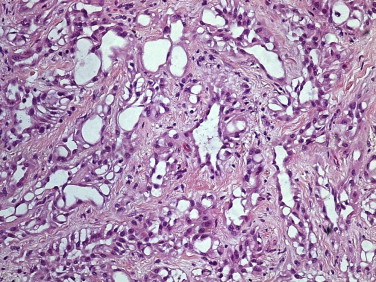

O estudo histológico revelou uma neoplasia formada por células epitelioides ou endotelioides dispostas em túbulos, cordões ou pequenos ninhos, de núcleo regular com pequeno nucléolo e citoplasma eosinófilo ou vacuolizado, conferindo por vezes uma morfologia tipo anel de sinete; estavam envolvidas por um estroma fibroso com discreto infiltrado linfocítico (fig. 1 ). A caracterização imuno‐histoquímica demonstrou positividade intensa e difusa para AE1/AE3 e calrretinina (Figura 2  ;  Figura 3 ), com negatividade para Ber‐Ep4. O diagnóstico histopatológico final foi de tumor adenomatoide paratesticular direito.

Tumor adenomatoide paratesticular – células epitelioides ou endotelioides ...

Figura 1.

Tumor adenomatoide paratesticular – células epitelioides ou endotelioides dispostas em túbulos, cordões e pequenos ninhos, de núcleo regular com pequeno nucléolo e citoplasma eosinófilo ou vacuolizado, conferindo por vezes uma morfologia tipo anel de sinete (HE 200 x).